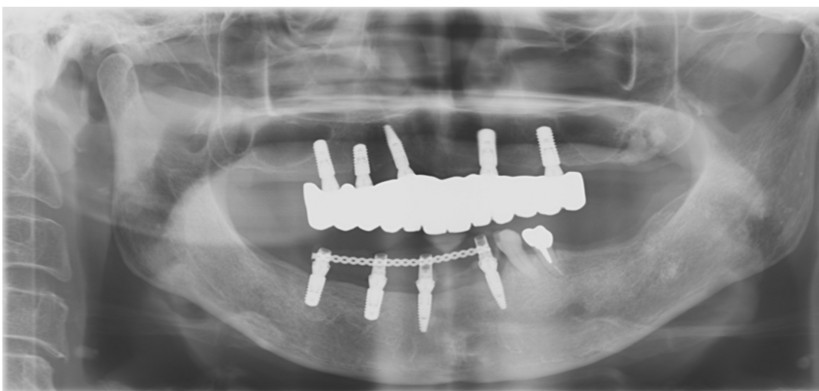

After

治療期間・回数

約6ヶ月・約6回

費用

23,100,000円

治療のリスク

外科手術が必要になるため、患者様に体力的な負担がかかる。